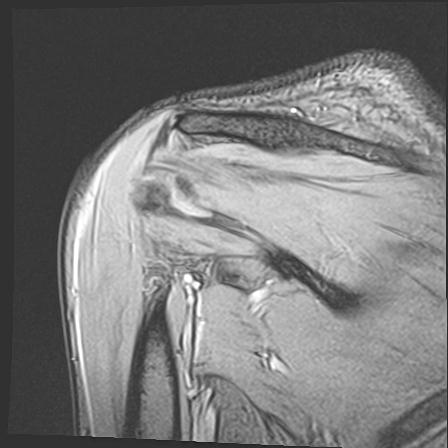

60058 3/9 11/4 右肩 2R+MRI 73歳男性 肩腱板損傷